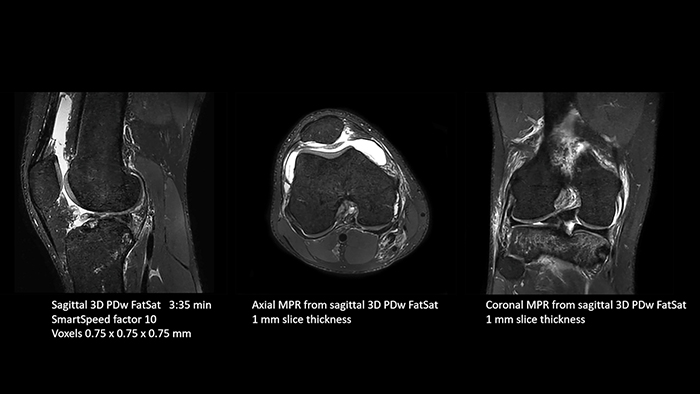

SmartSpeed is used to reduce scan times. All three PDw orientations were obtained with only one 3D sequence using SmartSpeed. Performed with 1.5T Ambition X, 16ch dS Knee coil.